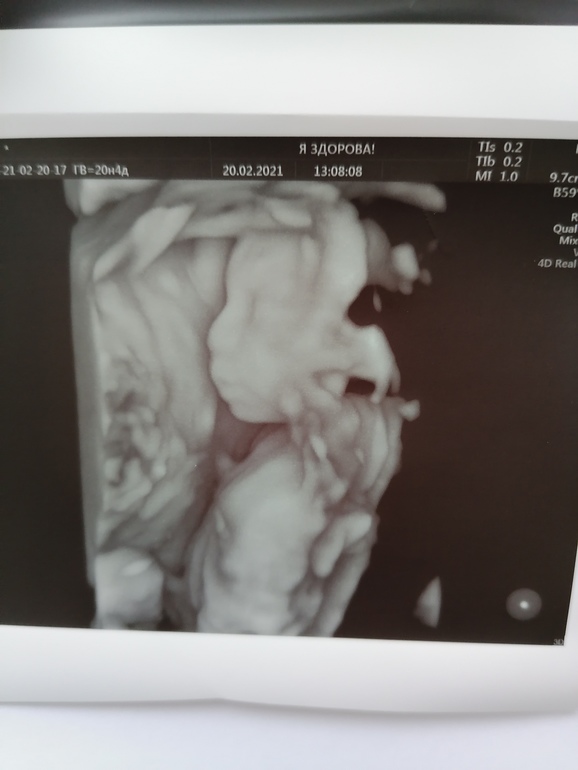

УЗИ прошло шикарно, врач меня вспомнила, все расспросила как и что. Всё рассмотрела идеально. Муж сидел с открытым ртом. Сделали нам аж 15 фото, прям фотосессия была у сыночка🥰😉. Он так мило зевал, язычком водичку ловил💙💙💙. Прям умиление сплошное🥰. Лежит головой вниз.

Ну и наши фоточки🥰👶🙏🙏🙏.

Ну и фотосессия сыночка👶🙏🙏🙏🥰.